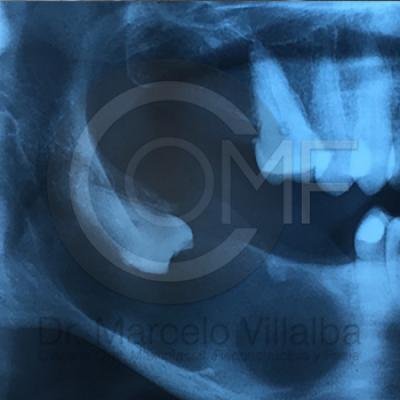

CIRUGÍA MAXILOFACIAL

Patología